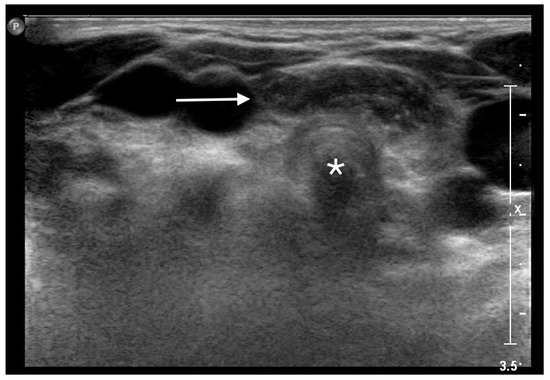

An MRI of the neck, carried out under general anesthesia, showed an orthotopic thymus, located into the anterior mediastinum, without any mass effect. After the MRI, a dynamic ultrasonography was carried out during the Valsalva maneuver, showing the superior herniation of a mass with the sonographic appearance of the normal thymus. The mass consisted of a roughly oval structure, with multiple linear hyperechoic septa, and scattered hyperechoic foci, giving a characteristic “speckled” or “starry sky” appearance. The ultrasound examination showed the intermittent superior movement of the thymus into the cervical region, reaching the cervical trachea, without any buckling or displacement of adjacent structures (Figure 1).

Figure 1.

Superior herniation of the normal mediastinal thymus in a 5-year-old girl. Transverse sonogram obtained during the Valsalva maneuver showing a roughly oval structure (white arrow) with the typical “starry sky” appearance of thymus, in front of the cervical trachea (white star).